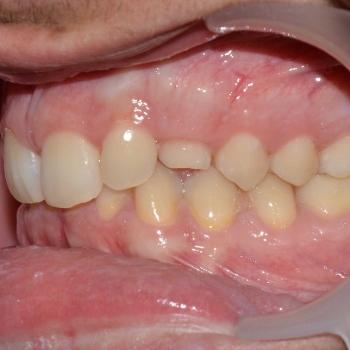

Ádám és édesanyja fogorvosuk javaslatára kerestek fel a felső állcsontban rekedt maradó szemfogak sorbaállításának kérésével. A panoráma röntgenfelvétel elemzése alapján egyértelművé vált, hogy a maradó szemfogak hibás tengelyállása okozta a tej szemfogak perzisztenciáját és a maradó szemfogak előtörésének a hiányát. A szemfogak 30 és 45 fokos dőlésének klinikai képet tovább árnyalták egyéb fogszabályozási eltérések is, mint például a mélyharapás, a nagymetszők közötti rés, illetve jobb oldali második nagyőrlők közötti fordított keresztharapás.

A probléma súlyosságát figyelembe véve, Ádám nagyon bölcsen az önligírozó fém fogszabályozó mellett döntött, melyet bite turbo harapásemelővel és különböző intermaxilláris gumihúzásokkal egészítettünk ki. Az önligírozó fogszabályozó ellenére a kezelés ideje igen hosszú volt. Ennek oka, hogy a szemfogak szájsebészeti feltárása közben derült fény a levontatantó fogak dőlésén kívüli 100-160 fokos tengely körüli elcsavarodására is.

Ádám kitartásának köszönhetően a kezelés végére minden maradó fog a helyére került és egy esztétikailag és funkcionálisan is tökéletes harapást kaptunk.